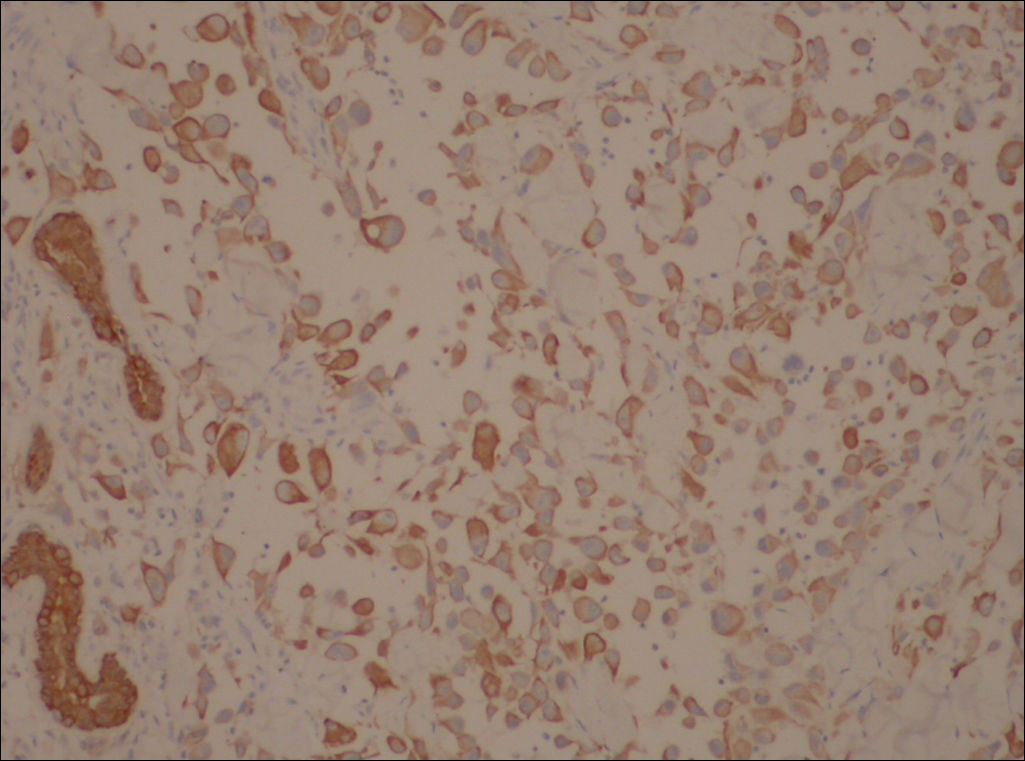

典型的假血管性鳞状细胞癌。

1、肿瘤细胞极度棘层松解而形成假血管腔和囊腔,内含淡蓝色粘液样物及渗出的红细胞。

2、腔壁衬有非典型上皮样细胞,多角形,排列方式小巢状、索条状,核空泡状,核仁明显。被覆皮肤上皮有发育不良现象。

免疫组化结果:

阳性:  CKVimCK5/6CK14

阴性:  MyoD1MyogeninDesminSMAEMACD34HMB45CK8/18CEA

特染:  AB-PAS(-)